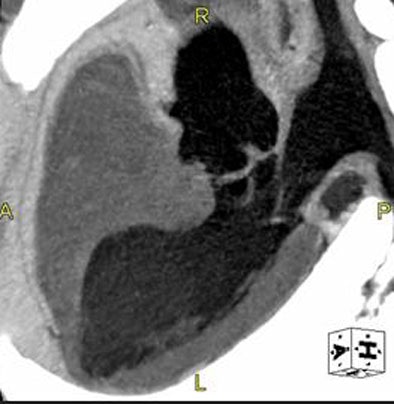

| By replacing contrast that would otherwise be wasted in the arm veins, saline flushing after contrast administration has several advantages including the saving of contrast media (approximately 15 mL) and a reduction in perivenous artifacts. Pure saline can be a disadvantage in cardiac CT functional studies, however, in which a complete lack of contrast media in the right ventricle (above) can render the intraventricular septum invisible. One possible solution is a 15% contrast media 85% saline mixture, which renders the intraventricular septum visible and solves the problem. Image courtesy of Dr. Dominik Fleischmann. . |

With saline, for example, "you can completely clear the right ventricle from contrast media, which improves the view of the right coronary artery," Fleischmann said. "One downside is if you have no contrast at all in the right ventricle, you cannot see the intraventricular septum of the heart, and if you can't see it, you are very limited in evaluating functional studies."

For this reason it helps to flush the venous system with a mixed solution rather than pure saline -- for example, 15% contrast, 85% saline -- which allows delineation of the septum, he said.